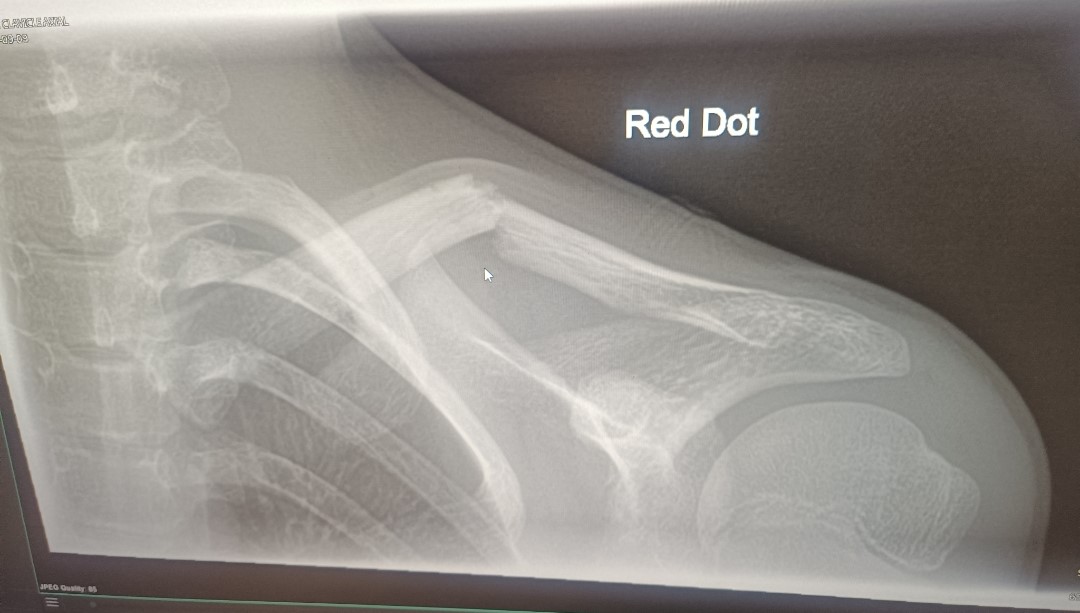

Chloe’s extraordinary achievements did not stop there. We were thrilled to learn that she had been selected to represent Wales again at the 2024 European Cup in Croatia, and the NBTA Europe Majorettes Championships in Eindhoven, Netherlands. Training an astonishing fifty hours per week, Chloe aimed to be in peak condition to compete. However, just three weeks before the Eindhoven competition, disaster struck. Chloe suffered a heart-wrenching setback after an horrific collarbone break sustained during a rugby tackle at school. The injury was severe, and the x-ray revealed a fracture that would leave her unable to train, after doctors issued Chloe strict orders to rest.